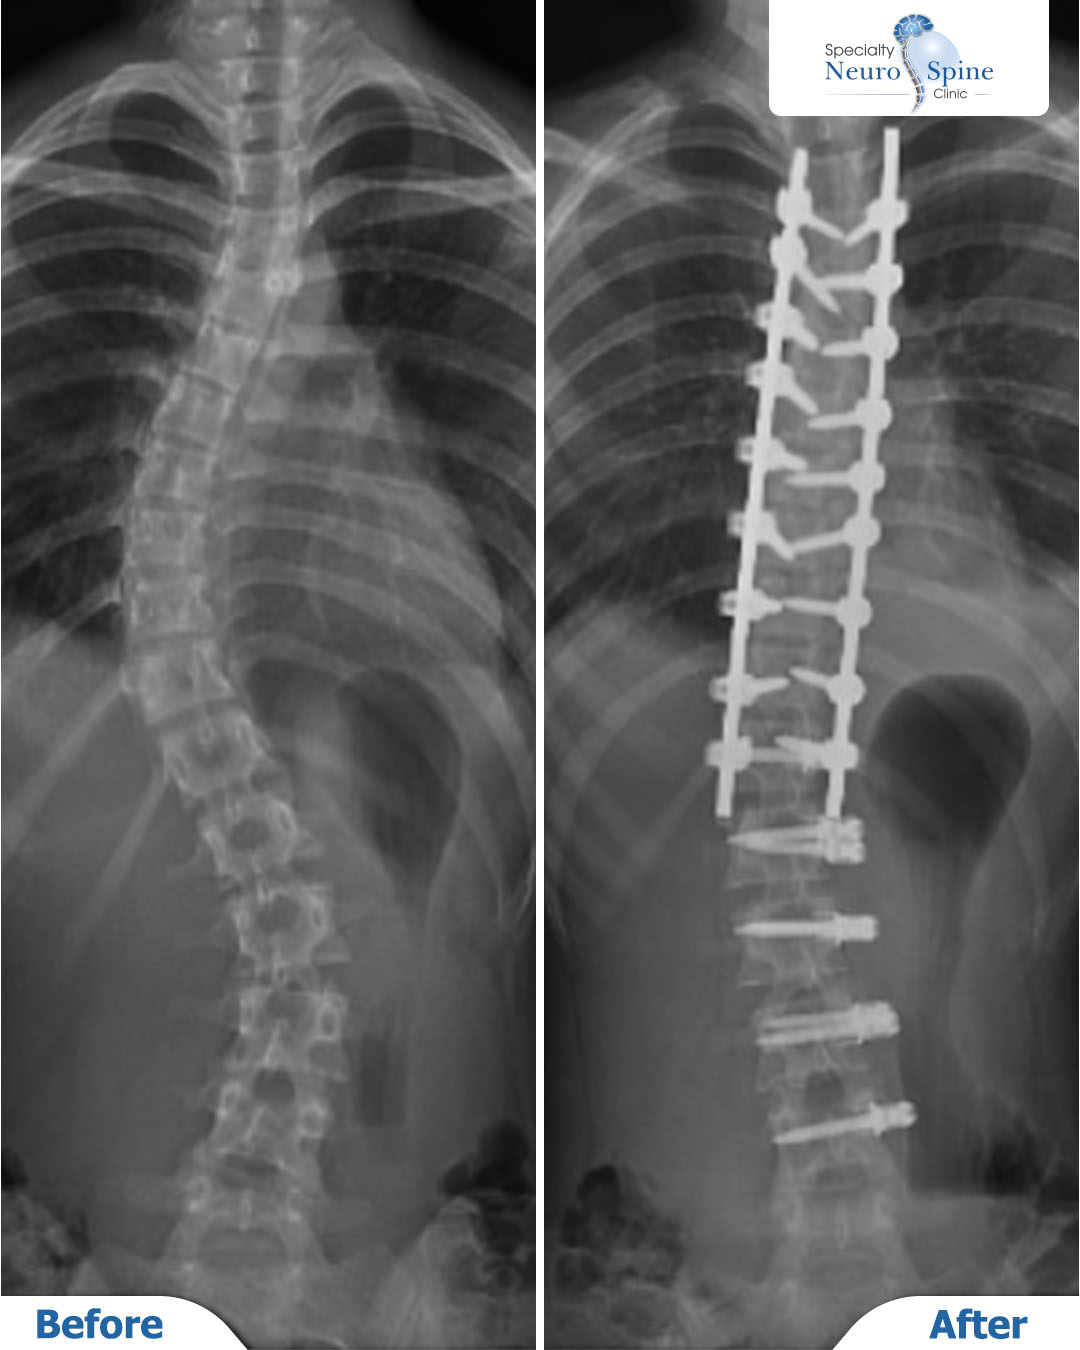

Before and after X-rays of our dear patient, Francis, a 14-year-old from the Philippines, who was suffering from progressive spinal curvature (scoliosis).

Dr. Firas Al-Hasban performed a corrective procedure involving Anterior Vertebral Body Tethering (VBT) using a flexible medical cord from T12 to L4, combined with posterior spinal fusion from T4 to T12.

The images demonstrate a significant improvement in spinal alignment post-surgery, achieving the desired balance while preserving flexibility in the lower spine.